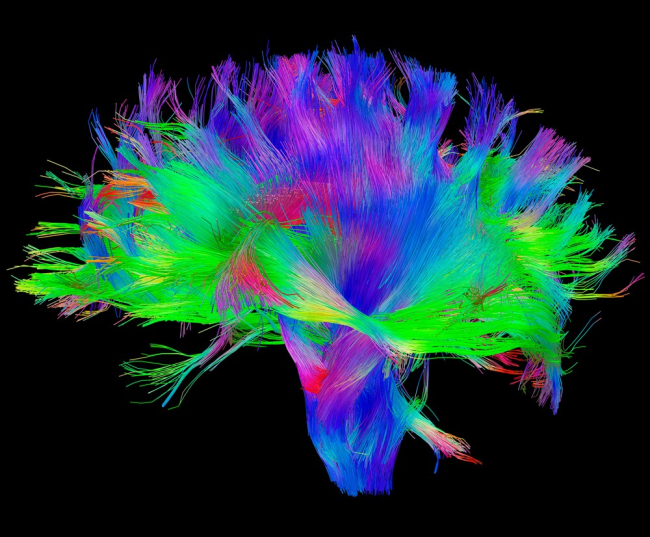

Уникальная система связей в мозгу индивида может быть использована для идентификации личности, подобно отпечаткам пальцев

Однако Эмили Финн (Emily Finn) и её коллеги выяснили, что уникальные особенности связей различных участков мозга человека достаточно стабильны, чтобы определять его личность в сравнении с другими индивидами.

Учёные работали со 126 участниками проекта «Коннектом человека». Оказалось, что рисунок связей, полученный в ходе одного из сеансов нейровизуализации (в состоянии покоя при прохождении тестов на память, эмоции и языковые навыки), в последующих сеансах остается неизменным и по нему легко определить индивида среди других участников эксперимента, сообщает «Лента.Ru».

Более того, рисунки связей помогли предсказать уровень подвижного интеллекта (способность воспринимать и запоминать новое, решать проблемы, с которыми человек раньше не сталкивался). Главными прогностическими факторами этой способности оказались связи между лобной, теменной и височной долями головного мозга.

В проекте «Коннектом человека», помимо Оксфордского университета, принимают участие университеты Вашингтона и Миннесоты. Коннектомом называют совокупность всех связей между нейронами, число которых в мозге человека оценивается в квадриллион. Проект был запущен в 2010 году, его бюджет составил $40 миллионов.